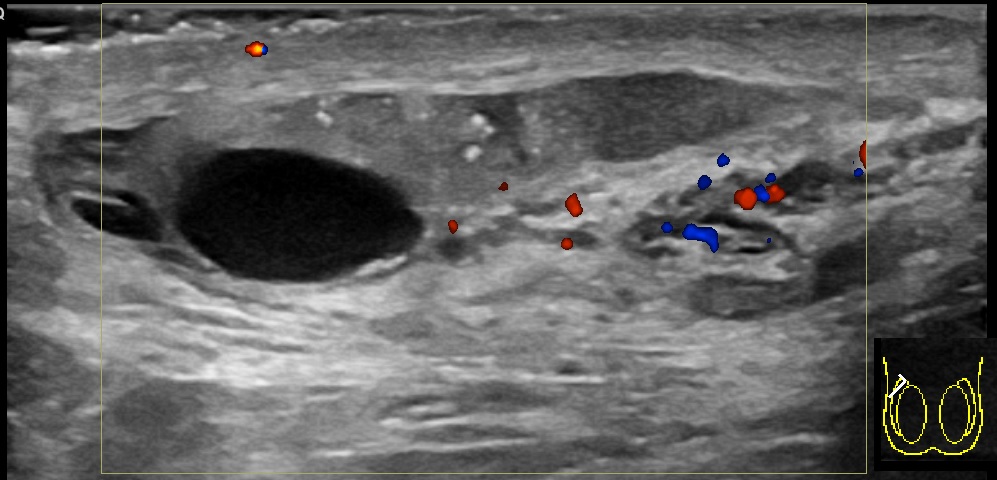

진단은 일반적으로 증상을 기반으로 한다.[1] 유사한 증상을 유발할 수 있는 질환으로는 고환 염전, 서혜부 탈장, 고환암 등이 있다.[1] 진단이 불분명한 경우 도플러 초음파 검사가 유용할 수 있다.[1]

정교한 의학 영상 기술이 개발되기 전에는 외과적 탐사가 표준 치료법이었다. 오늘날에는 도플러 초음파 검사가 일반적인 검사이다. 이는 혈류 영역을 보여주고 부고환염과 염전을 명확하게 구별할 수 있다. 그러나 염전 및 고환 통증의 다른 원인은 촉진만으로도 종종 확인할 수 있으므로, 일부 연구에서는 초음파의 유일한 실질적인 이점은 고환암이 없음을 환자에게 확신시키는 것이라고 제안했다.[10] 핵의학적 고환 혈류 검사는 드물게 사용된다.

정교한 의학 영상 기술이 개발되기 전에는 외과적 탐사가 표준 치료법이었다. 오늘날에는 도플러 초음파 검사가 일반적인 검사이다.[10] 이는 혈류 영역을 보여주고 부고환염과 염전을 명확하게 구별할 수 있다. 그러나 염전 및 고환 통증의 다른 원인은 촉진만으로도 종종 확인할 수 있으므로, 일부 연구에서는 초음파의 유일한 실질적인 이점은 고환암이 없음을 환자에게 확신시키는 것이라고 제안했다.[10] 핵의학적 고환 혈류 검사는 드물게 사용된다.